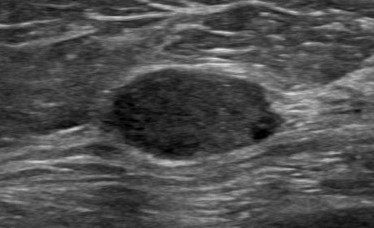

Gambar USG payudara menunjukkan perbedaan antara benjolan jinak dan kanker

Benjolan payudara kanker - menunjukkan margin tidak teratur dan tidak jelas (permukaan tajam dan tidak teratur seperti durian)

Gambar Ultrasonografi Payudara menunjukkan antara massa kistik (berisi cairan) dan padat

Payudara padat dengan margin tidak teratur - untuk menunjukkan massa payudara yang mencurigakan.